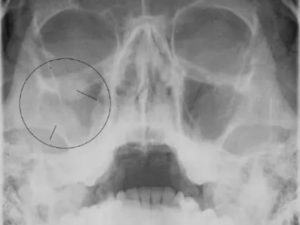

Взрослых специалист направляет на рентгеноскопию и ультразвуковое исследование. При недостатке информации назначает пункцию. Детям и беременным рентген противопоказан. Вместо него используют метод диафаноскопии, изучая области гайморовых пазух с помощью лампы Геринга.

- рентген-исследование пазух;

Локализацию болезни проще всего обнаружить на рентгеновском снимке. Патология отображается на нем в виде темных пятен различного объема.